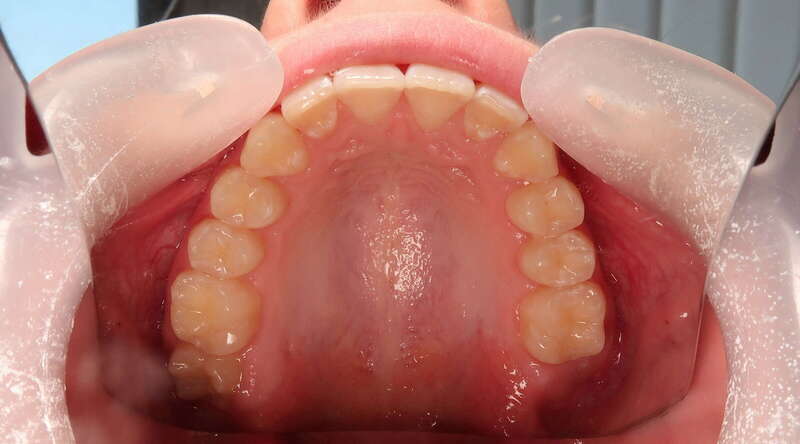

Cas n°1 traité par aligneurs (interception) - enfant

Ce cas d’interception chez un enfant de 8 ans démontre l'efficacité des aligneurs pour corriger des troubles fonctionnels précoces. Le diagnostic présentait des inversions d'articulé provoquant une déviation de la mandibule vers la gauche et un décalage des milieux.

Grâce à une coopération exemplaire et un traitement totalement indolore, l'expansion de l'arcade a permis de recentrer la mâchoire. Cette intervention a littéralement remis la croissance sur les rails, neutralisant le risque d'asymétrie faciale squelettique.

Avant

Après